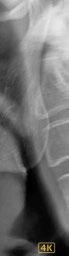

En la ortopantomografía se aprecia una dentición permanente a falta de la erupción de los 2os y 3 os molares, así como una asimetría ósea con rama y cóndilo mandibular izquierdo menos desarrollado (figura 9), causante de la asimetría facial descrita anteriormente.

Figuras 9-11.

vestibulizados (52º), e inferiores lingualizados (16 º). El perfil es extremadamente convexo.